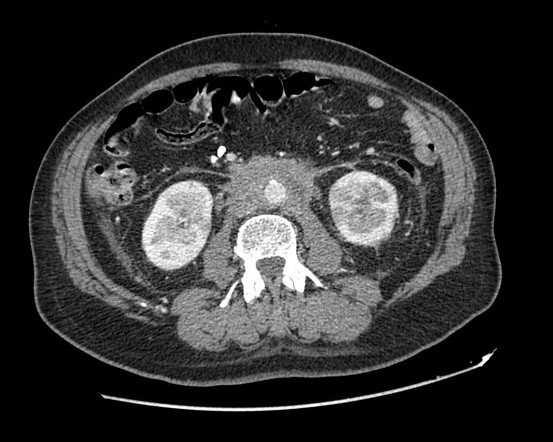

• Covers organ-wise involvement: pancreas, kidneys, glands, retroperitoneum, lymph nodes.